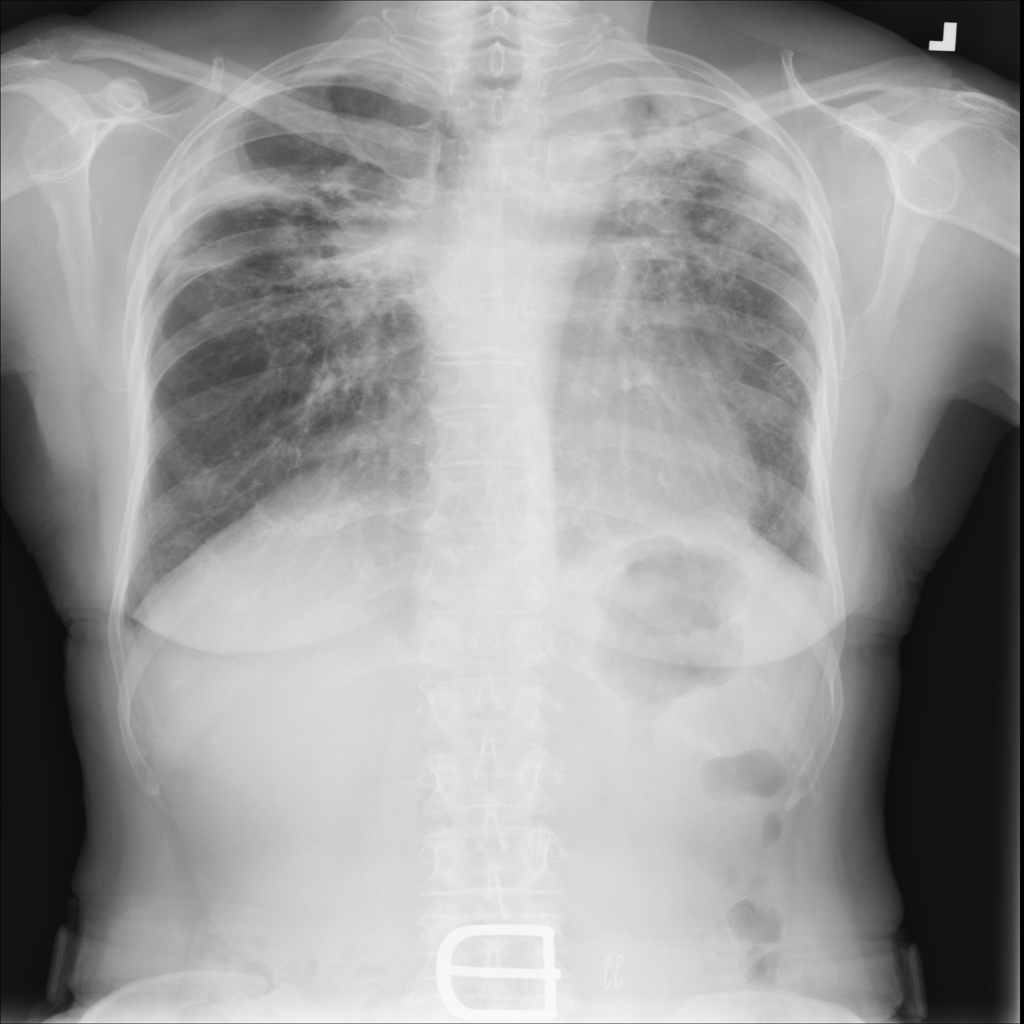

Showing up to 90 reference images for Fibrosis.

PAT-E066 · IMG-010Fibrosis

PAT-E066 · IMG-010

PA